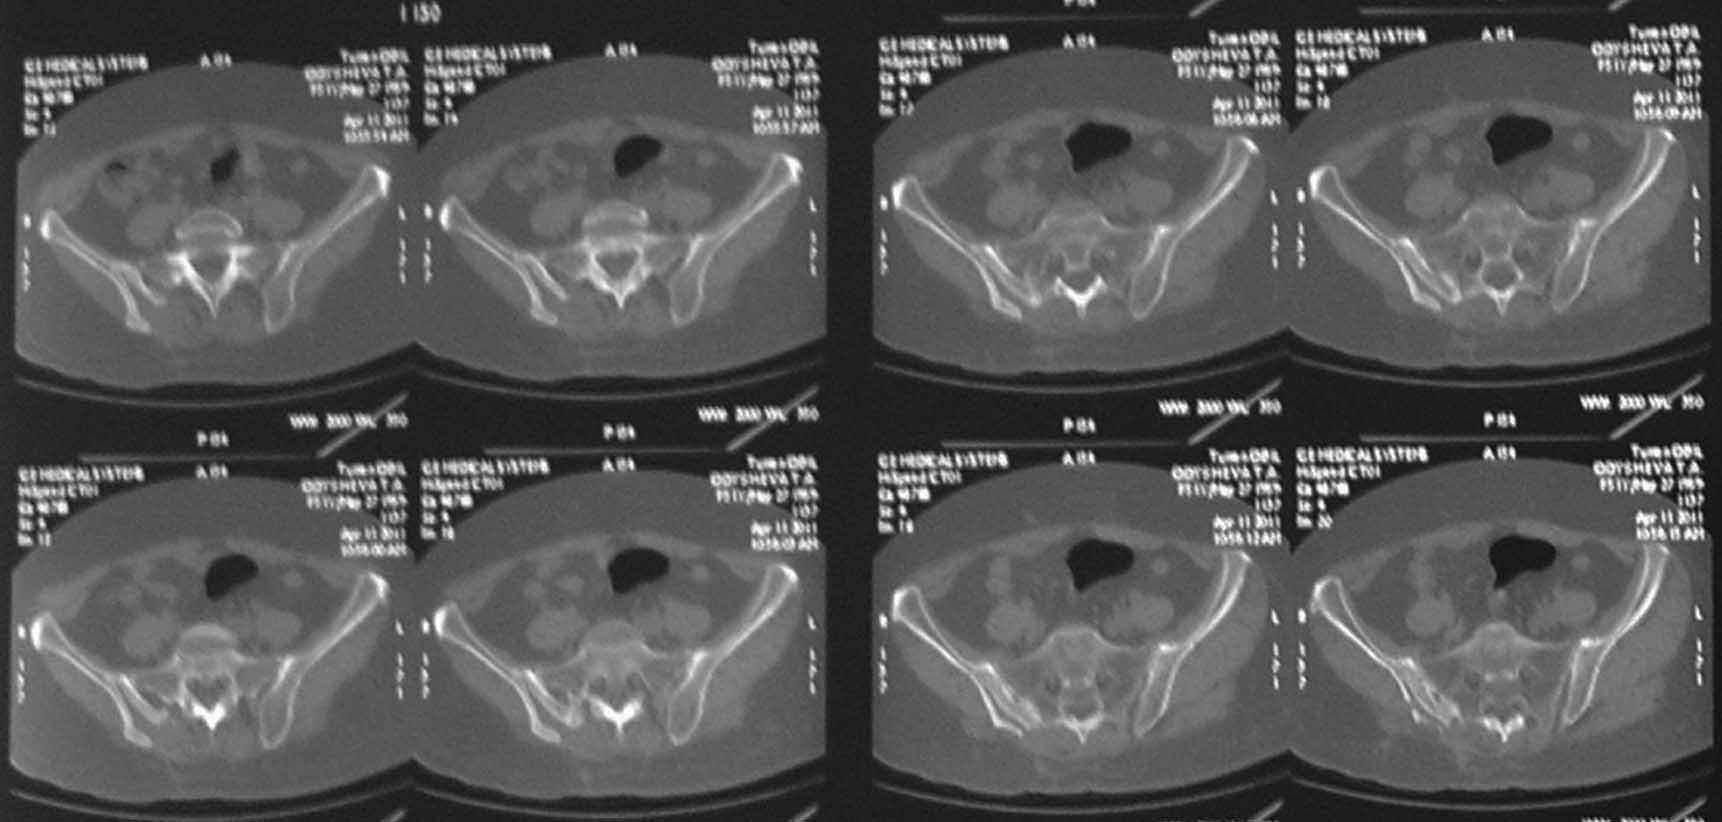

В 2009г установлен диагноз - сакроилеит справа.На представленных КТ имеется гипертрофия заднего отдела правой подвздошной кости с образованием контакта с задней поверхностью крестца.В январе 2011 года выполнена попытка удаления гипертрофированного участка подвздошной кости. удаленные участки кости исследованы гистологически - губчатая кость с элементами гиалинового хряща. После операции положительного эффекта не получено. На контрольной КТ от 04.2011 обнаружено что, желаемого результата операции не получено(интересующий участок удален частично), при этом имеется расслоение заднего отдела правой подвздошной кости.

На первичных КТ от 19-12-2009 определяется частичное анкилозирование правого крестцово-подвздошного сочленения, а на последних, от 11-04-2011 протяженность анкилозированной зоны значительно больше - сакроилеит прогрессирует, (с левой стороны вроде тоже признаки сакроилеита появились - не очень понятно из-за качества снимка). Значимых дуральных и радикулярных конфликтов действительно нет. "расслоение кости" - рентгенологически выглядит как травматический перелом подвздошной кости. Что делать? - наверное, искать серонегативные спондилоартропатии у ревматолога.